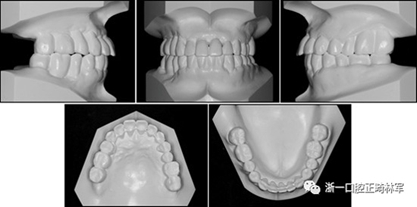

在治療結(jié)束時,通過拔除下頜側(cè)切牙,間隙閉合和推上頜牙列向遠中,實現(xiàn)了前牙良好的對齊,尖牙I類關(guān)系以及合適的覆合和覆蓋?;颊叩膫?cè)面貌輪廓得到改善,并且她的嘴唇不適得到緩解。下頜右側(cè)第二磨牙直立,后牙被修復(fù)并恢復(fù)穩(wěn)定咬合(圖10和圖11)。牙周治療和牙周病的控制導(dǎo)致牙周袋深度的穩(wěn)定,并且在探測時沒有出血。

圖11.治療后牙齒的石膏模型